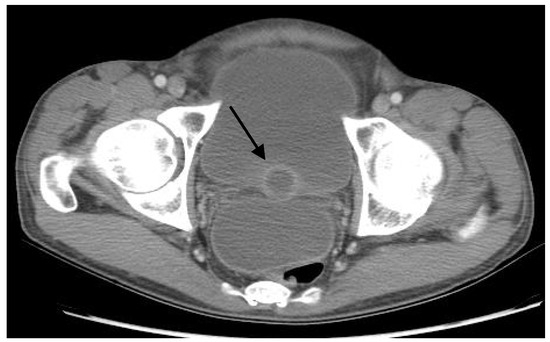

Physical exam was notable for a temperature of 100.9°F (38.3°C) and blood pressure of 80/54 mmHg. His abdomen was firm, tender, and distended. He refused a digital rectal exam. He was HIV negative on the rapid HIV immunoassay. Urinalysis was notable for pyuria; urine bacterial culture demonstrated no growth, and urine AFB smears were negative. His chest radiograph was unremarkable. Computed tomography (CT) of the abdomen and pelvis with intravenous and oral contrast revealed large- volume ascites, diffuse peritonitis, multiple prostatic abscesses (largest 3.5 cm) (Figure 1), and possible focal pyelonephritis in the left kidney.

Figure 1.

Computed tomography (CT) of the abdomen and pelvis with intravenous and oral contrast demonstrating prostatic abscess (arrow).